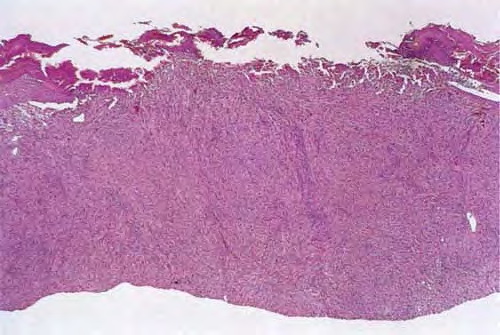

Atrophic lichen planus = الحزاز المنبسط الضموري